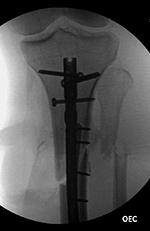

| Male patient with proximal tibia and fibula fractures treated by intramedullary nail and supplemental one-third tubular plate. Initial intraoperative fluoroscopic AP and lateral images (left two images) show the plate (arrow on lateral image). The patient ambulated against advice and was lost to follow-up. Two months later he again presented (right two images) to the clinic. There is now tibia fracture migration, and the proximal medial to lateral interlocking screw has backed out (AP view). The lateral view demonstrates fracture displacement with flexion deformity. The nail has troughed outside the proximal anterior tibia and is sitting within the soft tissues. The supplementary plate is broken, there is a broken interlocking screw, and abundant fracture callus is present. |